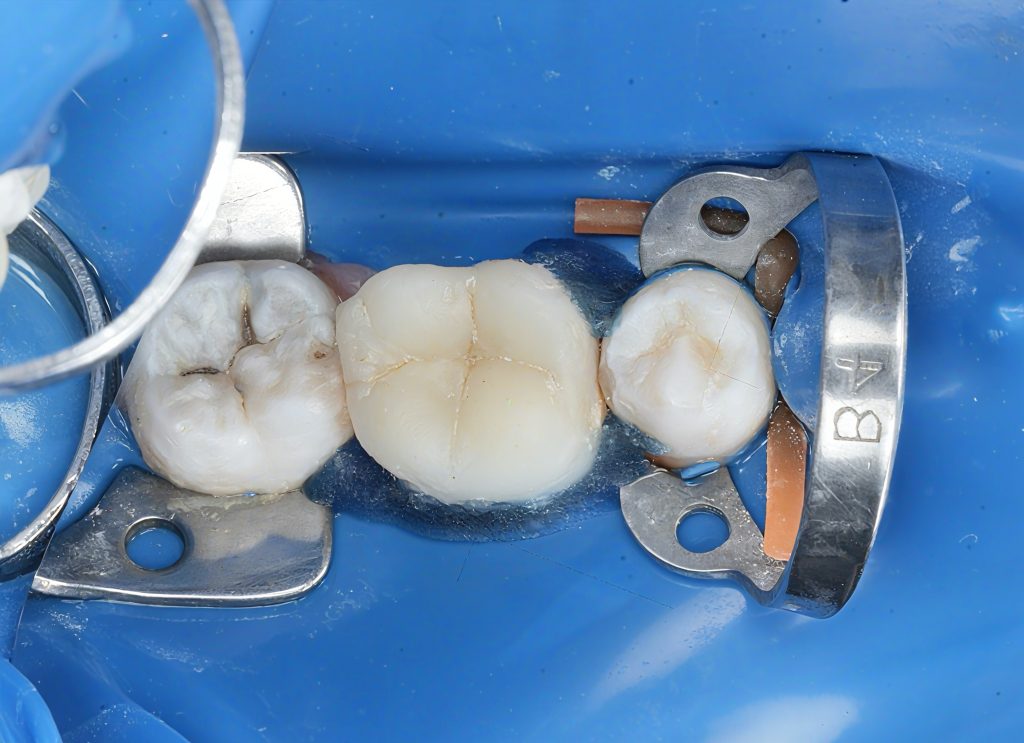

2. Isolation & Access

(Images 2–3)

Full rubber dam isolation for contamination control. Previous fillings removed, caries outlined, and access refined under magnification.